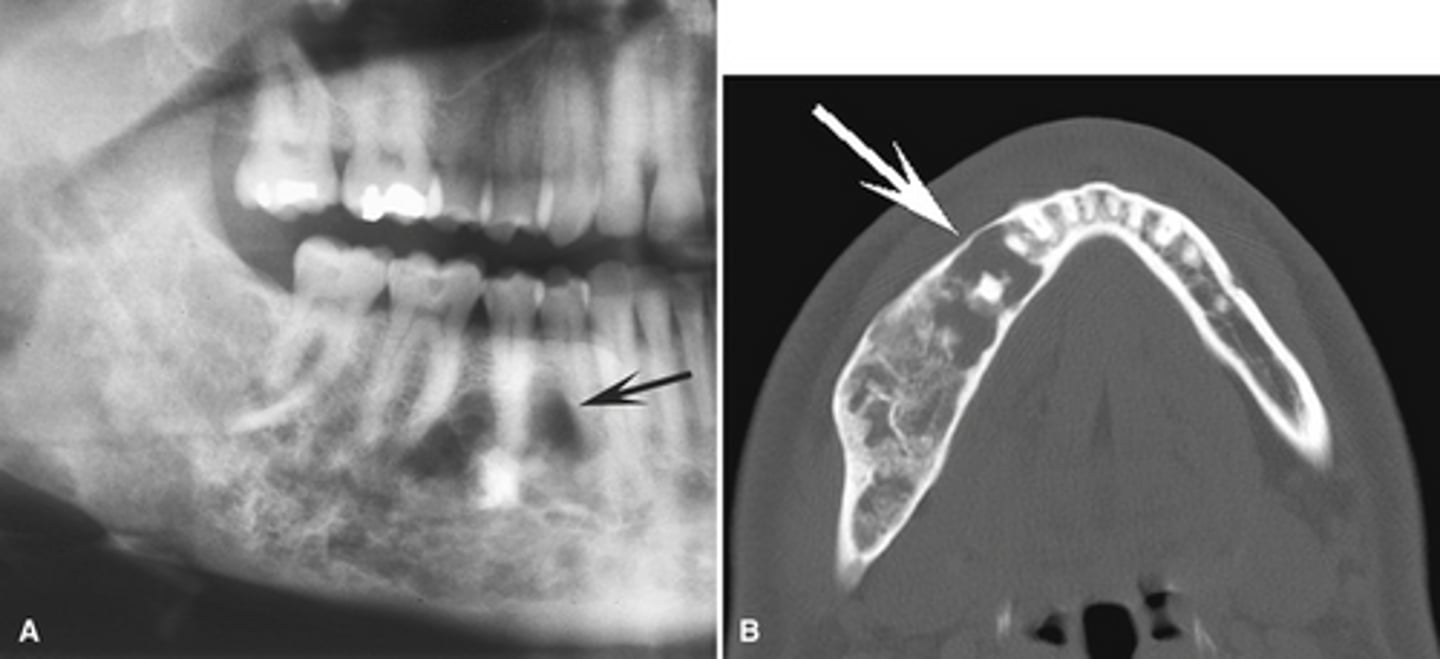

hyperparathyroidism; Brown tumor (aka central giant cell granuloma)

The top images show show loss of lamina dura around the teeth in a patient with _____________. The bottom image shows ________ developing under the molar?

Brown tumor in a patient with hyperparathyroidism

What is the pathology in the radiographs?